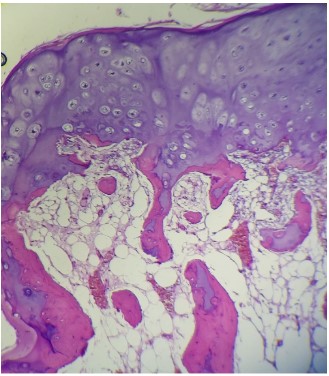

Histopathologic exam confirmed the diagnosis of osteochondroma with bony trabeculae,enchondral ossification and hyaline cartilage cap (Figure 6). The child has recovered from these sensitive neurological disorders with no local recurrence at follow up (Figure 7).

Figure 6: H&E x 200 the lesion shows hyaline cartilage cap underlying an area of enchondral ossification followed by mature bony trabeculaeconttaining normal bone marrow.